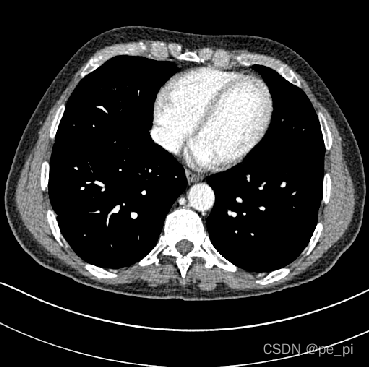

return Hu(2)获得HU为单位的图像的矩阵后,需要针对HU图像进行调窗,以适应于我们对不同部位的图像进行分析(医学图像中不同部位的适用的HU范围不同,这个范围叫做窗口),在imageJ中窗口的大小叫做window,窗口的中心叫做level,在这几个参考的帖子中有不同的叫法,在此按照ImageJ 的名称[5,6]。

return norm_调窗后的数据就是想要查看的数据范围了,在这里对不同部位调窗的数据值设定也不相同[7].